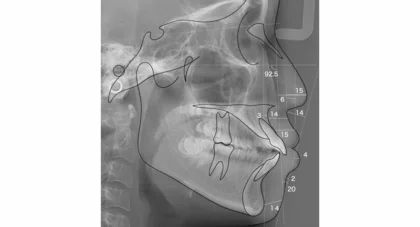

矯正治療の効果を最大限に引き出すには、正確で綿密な診断が欠かせません。当院では、セファロレントゲンや歯科用CTに加え、AIを活用したデジタル診断で歯並びや噛み合わせを精密に把握し、治療後のシミュレーションも行います。一般的な歯科医院では行われない軟組織分析や気道評価にも対応し、骨格や顔貌のバランスまで考慮。必要に応じて医科と連携した精密検査も取り入れることで、より総合的で安全な治療計画を立案しています。

硬組織分析・軟組織分析

横顔のバランスや唇の位置、顎のラインなど、見た目の美しさや自然な表情に関わる部分を評価。笑ったときの印象や横顔のシルエットまで考慮することで、より自然で調和のとれた仕上がりを目指せます。硬組織分析

骨格のズレやバランス

軟組織分析

唇や顎の位置

気道評価

睡眠時無呼吸症候群などのリスクも確認し、呼吸機能に配慮した治療計画を立てます。